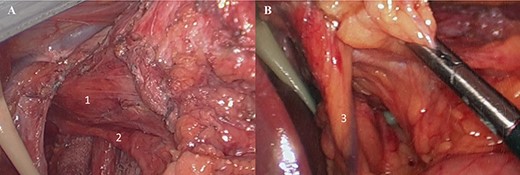

The patient underwent an elective laparoscopic surgical revision. Intraoperatively, majority of the SG had herniated into supradiaphragmatic position through the diaphragmatic esophageal hiatus and had a partial organoaxial volvulus (Fig. 2). Lysis of adhesion was carried with full mobilization of the SG and distal esophagus were achieved. The intrathoracic SG was reduced followed by the excision of the hernia sac with preservation of anterior and posterior vagus nerves and the left gastric artery (Fig. 3). The esophageal hiatus diaphragmatic defect was closed with four figure of eight stitches posterior to the esophagus using braided zero polyester (Fig. 4A). A relative narrowing of the mid portion of the SG at the incisura and an excess of gastric fundus was present. A 4 cm long gastric pouch was created in a standard fashion and the remnant of the SG was excised (Fig. 4B and C). Then a standard jejuno-jejunostomy (J-J) was done with a biliopancreatic limb of 60 cm and alimentary limb of 100 cm and the gastro-jejunal anastomosis was created using a 25 mm/4.8 mm circular stapler and reinforced with Lambert sutures of 3–0 polyglactin (Fig. 4D). The J-J and Peterson mesenteric defects were closed. Intraoperative leak test was negative.

(A) Laparoscopic view (1: distal esophagus, 2. posterior vagus nerve); (B) 3. left gastric artery.